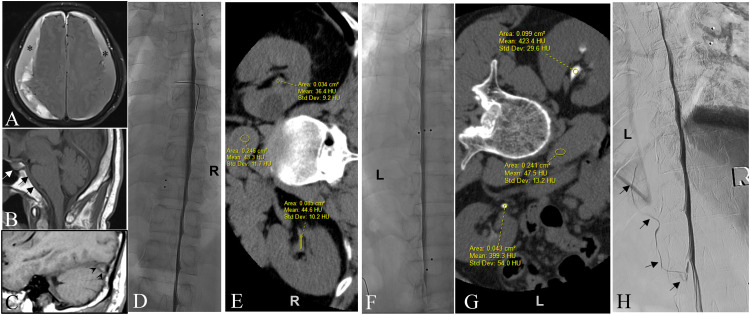

目的本文介绍了一种顺序侧卧数字减影脊髓造影(LDDSM)与侧卧CT (LDCT)密切配合的策略,以促进脑脊液(CSF)-静脉瘘(CVF)定位。材料与方法回顾性分析来我院评估脑脊液泄漏的患者。排除1型和2型渗漏患者,以及未出现颅内低血压的MR脑污点的患者。所有患者均连续行ldddsm和LDCT。如果CVF未定位在第一对ldsm - ldct上,则患者返回进行对侧检查。检查CVF和肾盂内造影剂积累的图像,以Hounsfield单位(HU)的肾盂造影剂评分(rpc)表示。结果本组共纳入22例患者。22例患者中有21例(95%)被确定为CVF,与CVF同侧的ldsm - ldct对的RPCS范围为71至423,平均为146 HU。8例患者在CVF对侧的LDDSM-LDCT对阴性侧的RPCS,平均为51 HU。在4例患者中,最初的双侧LDDSM- ldct对未显示CVF的位置,但在这4例中,有3例在第三个LDDSM上显示了CVF,重复到较高RPCS的同侧。结论序贯LDDSM-LDCT结合造影剂肾脏积聚评价策略可提高CVF的定位率,值得进一步评价。

PurposePresented here is a strategy of sequential lateral decubitus digital subtraction myelography (LDDSM) followed closely by lateral decubitus CT (LDCT) to facilitate cerebrospinal fluid (CSF)-venous fistula (CVF) localization.Materials and MethodsThis is a retrospective analysis of patients referred to our institution for evaluation of CSF leak. Patients with Type 1 and Type 2 leaks, and those not displaying MR brain stigmata of intracranial hypotension were excluded. All patients underwent consecutive LDDSM and LDCT. If the CVF was not localized on the first LDDSM-LDCT pair the patient returned for contralateral examinations. Images were reviewed for CVF and for accumulation of contrast within the renal pelvises expressed as a renal pelvis contrast score (RPCS) in Hounsfield units (HU).ResultsTwenty-two patients were included in this study. In 21 of 22 patients (95%) a CVF was identified yielding an RPCS for the LDDSM-LDCT pair ipsilateral to the CVF ranging from 71 to 423 with an average of 146 HU. An RPCS of the negative side LDDSM-LDCT pair contralateral to a CVF was available in 8 patients and averaged 51 HU. In 4 patients the initial bilateral LDDSM-LDCT pairs did not reveal the location of the CVF however in 3 of these 4 cases the CVF was revealed on a third LDDSM repeated ipsilateral to the higher RPCS.ConclusionThe strategy of sequential LDDSM-LDCT coupled with evaluation of renal accumulation of contrast agent appears to improve the rate of CVF localization and warrants further evaluation.